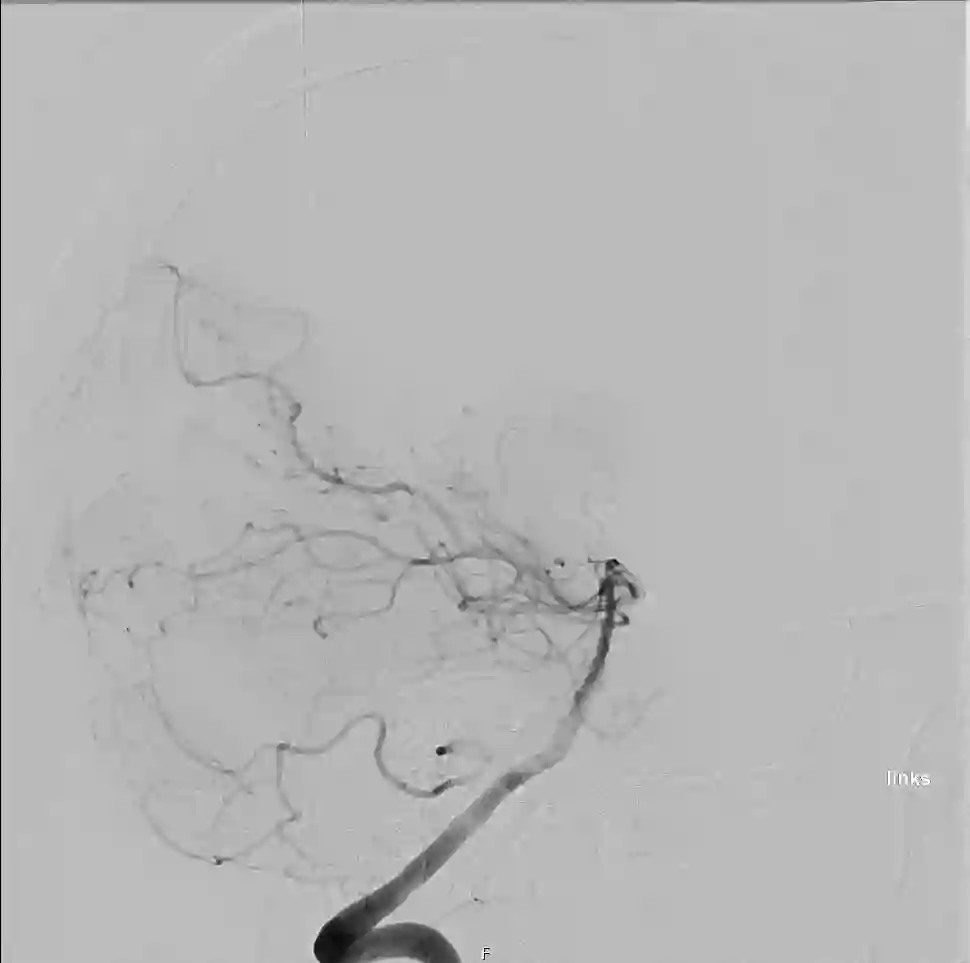

Darstellung eines unauffälligen hinteren Stromgebiets mit Hilfe einer digitalen Subtraktionsangiographie.